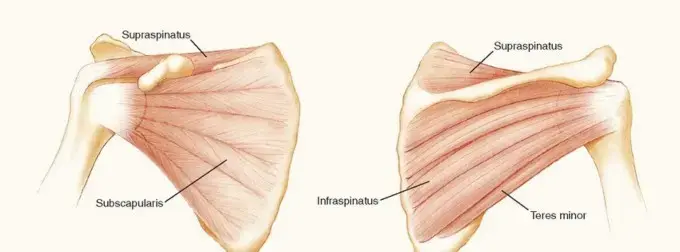

لفهم خلع الكتف المزمن، من الضروري أن نلقي نظرة سريعة على تشريح مفصل الكتف وكيف يعمل. يُعد مفصل الكتف، أو المفصل الحقاني العضدي، مفصلاً كروياً حُقيّاً، مما يعني أن رأس عظم العضد المستدير يستقر داخل تجويف ضحل يُعرف بـ "الحُق" (Glenoid) الموجود في لوح الكتف. هذا التصميم يمنح الكتف مرونة هائلة، ولكنه يجعله أيضاً غير مستقر بطبيعته مقارنة بمفاصل أخرى مثل مفصل الورك.

- رأس عظم العضد (Humeral Head): الجزء العلوي المستدير من عظم الذراع، والذي يتحرك داخل تجويف الحُق.

- الحُق (Glenoid): تجويف ضحل على لوح الكتف يستقبل رأس عظم العضد. هذا التجويف ليس عميقاً بما يكفي لاحتواء رأس العضد بالكامل، مما يفسر سبب سهولة خلع الكتف.

- الشفا الحقانية (Labrum): حلقة من الغضروف الليفي تحيط بحافة الحُق، وتعمل على تعميق التجويف وزيادة استقرار المفصل، بالإضافة إلى كونها نقطة ارتكاز لأربطة الكتف.

- المحفظة المفصلية (Joint Capsule): نسيج ضام قوي يحيط بالمفصل بأكمله، ويحتوي على السائل الزليلي الذي يزيت المفصل. في حالات الخلع المزمن، قد تصبح هذه المحفظة متمددة وسميكة.

- الأربطة (Ligaments): أشرطة قوية من النسيج الضام تربط العظام ببعضها البعض وتوفر استقراراً إضافياً للمفصل. أهمها الأربطة الحقانية العضدية.

- العضلات المدورة (Rotator Cuff Muscles): مجموعة من أربع عضلات (فوق الشوكة، تحت الشوكة، تحت الكتف، مدورة صغيرة) وأوتارها تحيط بمفصل الكتف، وتعمل على تثبيته وتحريكه في اتجاهات مختلفة. ضعف هذه العضلات أو تمزقها يزيد من خطر الخلع.

- النواتئ العظمية: مثل الناتئ الغرابي (Coracoid Process) والناتئ الأخرمي (Acromion)، وهما جزءان من لوح الكتف يوفران نقاط ارتكاز للعضلات والأربطة.

عند حدوث خلع، ينفصل رأس عظم العضد عن الحُق. في معظم الحالات، يكون الخلع أمامياً سفلياً، حيث يتجه رأس العضد إلى الأمام والأسفل. في حالة الخلع المزمن، تبقى هذه الأجزاء منفصلة لفترة طويلة، مما يؤدي إلى تغيرات هيكلية في العظام المحيطة، مثل تآكل حافة الحُق (آفة بانكارت العظمية) أو انخفاض في رأس العضد (آفة هيل ساكس)، بالإضافة إلى تمدد أو تمزق الأربطة والمحفظة المفصلية. هذه التغيرات تجعل استعادة وظيفة الكتف الطبيعية أمراً معقداً يتطلب خبرة جراحية متخصصة.